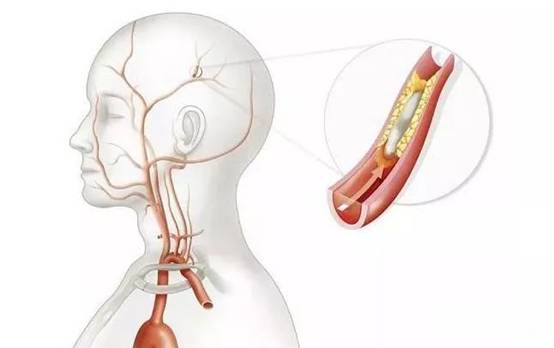

脑梗死是由脑供血动脉缺血所致,大多数脑梗死是由血栓形成及血栓栓塞引起的脑内动脉闭塞。在脑梗死早期,梗死中心部位是不可逆性坏死,如果及时恢复脑血流和改善脑组织代谢就可以挽救脑梗死周围的半暗带组织,避免形成永久性坏死(脑梗死)。因此,使血管再通复流是目前最好的治疗方法。血管再通复流可以通过静脉溶栓、动脉溶栓及动脉取栓等方法来实现。脑卒中发生后,脑组织超过一定时间(数分钟到数小时)即发生坏死,而发病后的4.5小时堪称黄金治疗时间窗。国际上也很早就提出了“时间就是大脑,时间就是生命”的救治理念。因此,必须争分夺秒尽早到医院就诊和治疗。缺血性脑卒中治疗上现全世界最有效的方案就是溶栓治疗,缺血性卒中患者接受溶栓治疗有显著获益。常规采取的是静脉溶栓治疗,对于一部分静脉溶栓效果不佳或怀疑大动脉狭窄的患者,有条件的机构可考虑采取动脉溶栓或取栓治疗。不管是溶栓治疗或其他治疗,对于缺血性脑卒中治疗,治疗时间越早,患者预后相应越好。